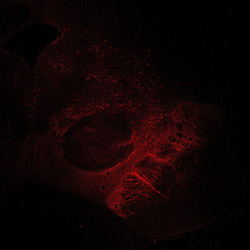

An anatomical analysis of the developing human midbrain from 6 post-conceptional weeks (PCW) to 22 PCW reveals increased tissue complexity, characterized by the emergence of dopaminergic nuclei, as highlighted by immunofluorescence analysis for tyrosine hydroxylase (TH).

12PCW

13PCW human midbrain